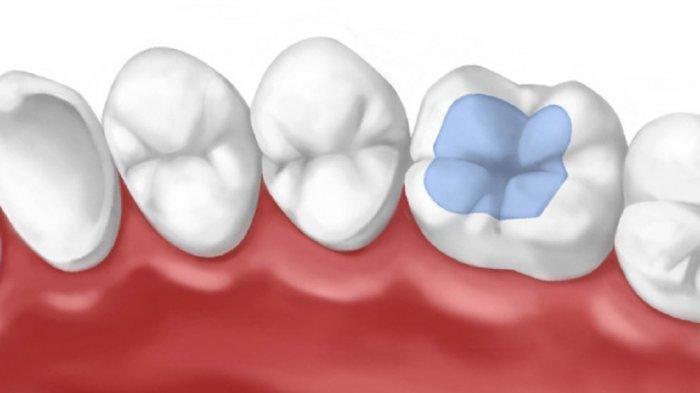

Untuk mengatasi masalah gigi berlubang dilakukan restorasi.

Restorasi adalah hasil dari prosedur kedokteran gigi yang bertujuan mengembalikan bentuk, fungsi, dan penampilan gigi.

Restorasi gigi adalah tambalan gigi pada gigi berlubang sedangkan fissure sealant adalah tambalan pada gigi yang akan berlubang.

Untuk mengatasi lubang kehitaman pada gigi dilakukan tindakan fissure sealant pada gigi tersebut untuk menghilangkan bercak hitam tersebut dan menghentikan proses demineralisasi yang terjadi, sehingga tidak memperluas atau memperdalam lubang gigi yang dibentuk.

Bagaimana bentuk bahan fissure sealant yang digunakan?

Apakah bahan fissure sialant berbentuk padat dok?

Bahan ini dikeraskan dengan bantuan sinar atau dengan menggunakan bahan dasar glass ionomer.